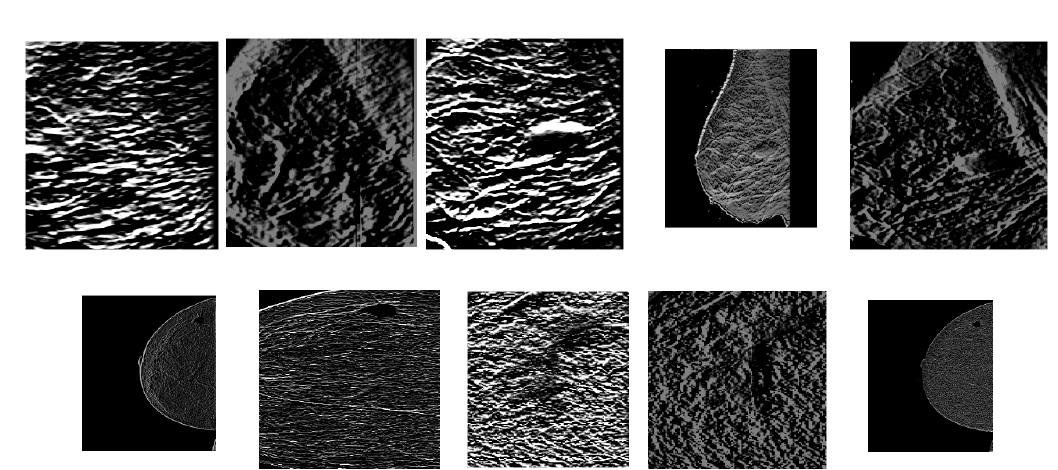

Breast cancer is one of the most leading causes of cancer deaths among women. Early detection of cancer increases the survival rate of the affected women. Machine learning approaches that are used for classification of breast cancer usually takes a lot of processing time during the training process. This paper attempts to propose a Machine Learning approach for breast cancer detection in mammograms, which does not depend on the number of training samples. The paper aims to develop a core vector machine-based diagnosis system for breast cancer detection using the date from MIAS. The main motivation behind using this system is to reduce the computational and memory requirement for large training data and to improve the classification accuracy. The proposed method has four stages: 1) Pre-processing is done to extract the breast region using global thresholding and enhancement using histogram equalization; 2) identification of potential mass using Otsu thresholding; 3) feature extraction using Laws Texture energymeasures; and 4) mass detection is done using Core vector machine (CVM) classfier. Comparative analysis was done with different existing algorithms: Artificial Neural Network (ANN), Support Vector Machine (SVM), and Fuzzy Support Vector Machines (FSVM). The results illustrate that the proposed Core Vector Machine (CVM) classifier produced a promising result in terms of sensitivity (96.9%), misclassification rate (0.0443) and accuracy (95.89%). The time taken for training process is 0.0443, which is less when compared with other machine learning algorithms. Conclusion: Performance analysis shows that CVM classifier is superior to other classifiers like ANN, SVM and FSVM. The computational time of the CVM classifier during the training process was also analysed and found to be better than other discussed algorithms. The results achieved show that CVM classifier is the best algorithm for breast mass detection in mammograms.